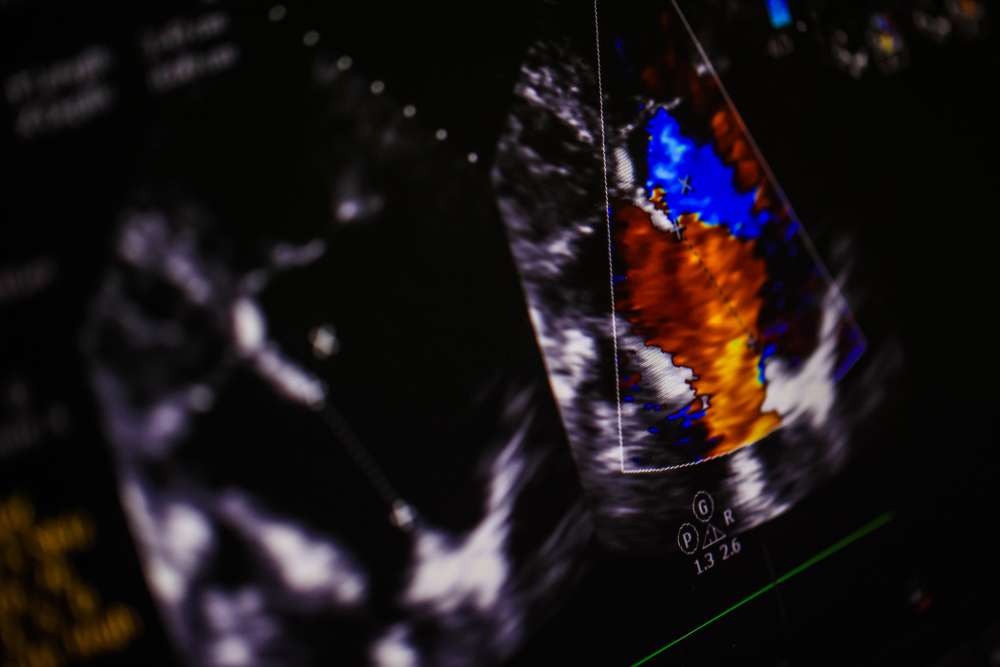

The good news in all of this is that despite the potential variety of diagnoses, determining a murmur's innocence isn't an invasive or traumatic experience. Echocardiograms "are so straightforward," Ryan says. "There's no radiation, no stress, and no trauma. No damage can come from it."